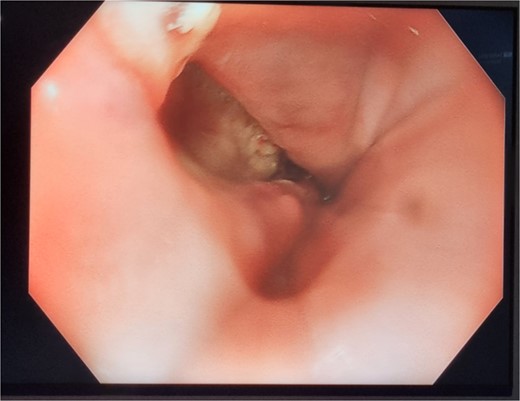

On day 2 post-diagnosis, the patient underwent an OGD, VACStent insertion, and ultrasound-guided pleural drain placement. The endoscopy revealed a 2 cm linear defect in the lower oesophagus just above the gastroesophageal junction (Fig. 3), and the VACStent was connected to 125 mmHg of negative pressure, confirming appropriate positioning. The patient tolerated the procedure well without intraoperative complications and was transferred to the ICU intubated.

Patient Three: Before VACStent insertion, showing the oesophageal defect.